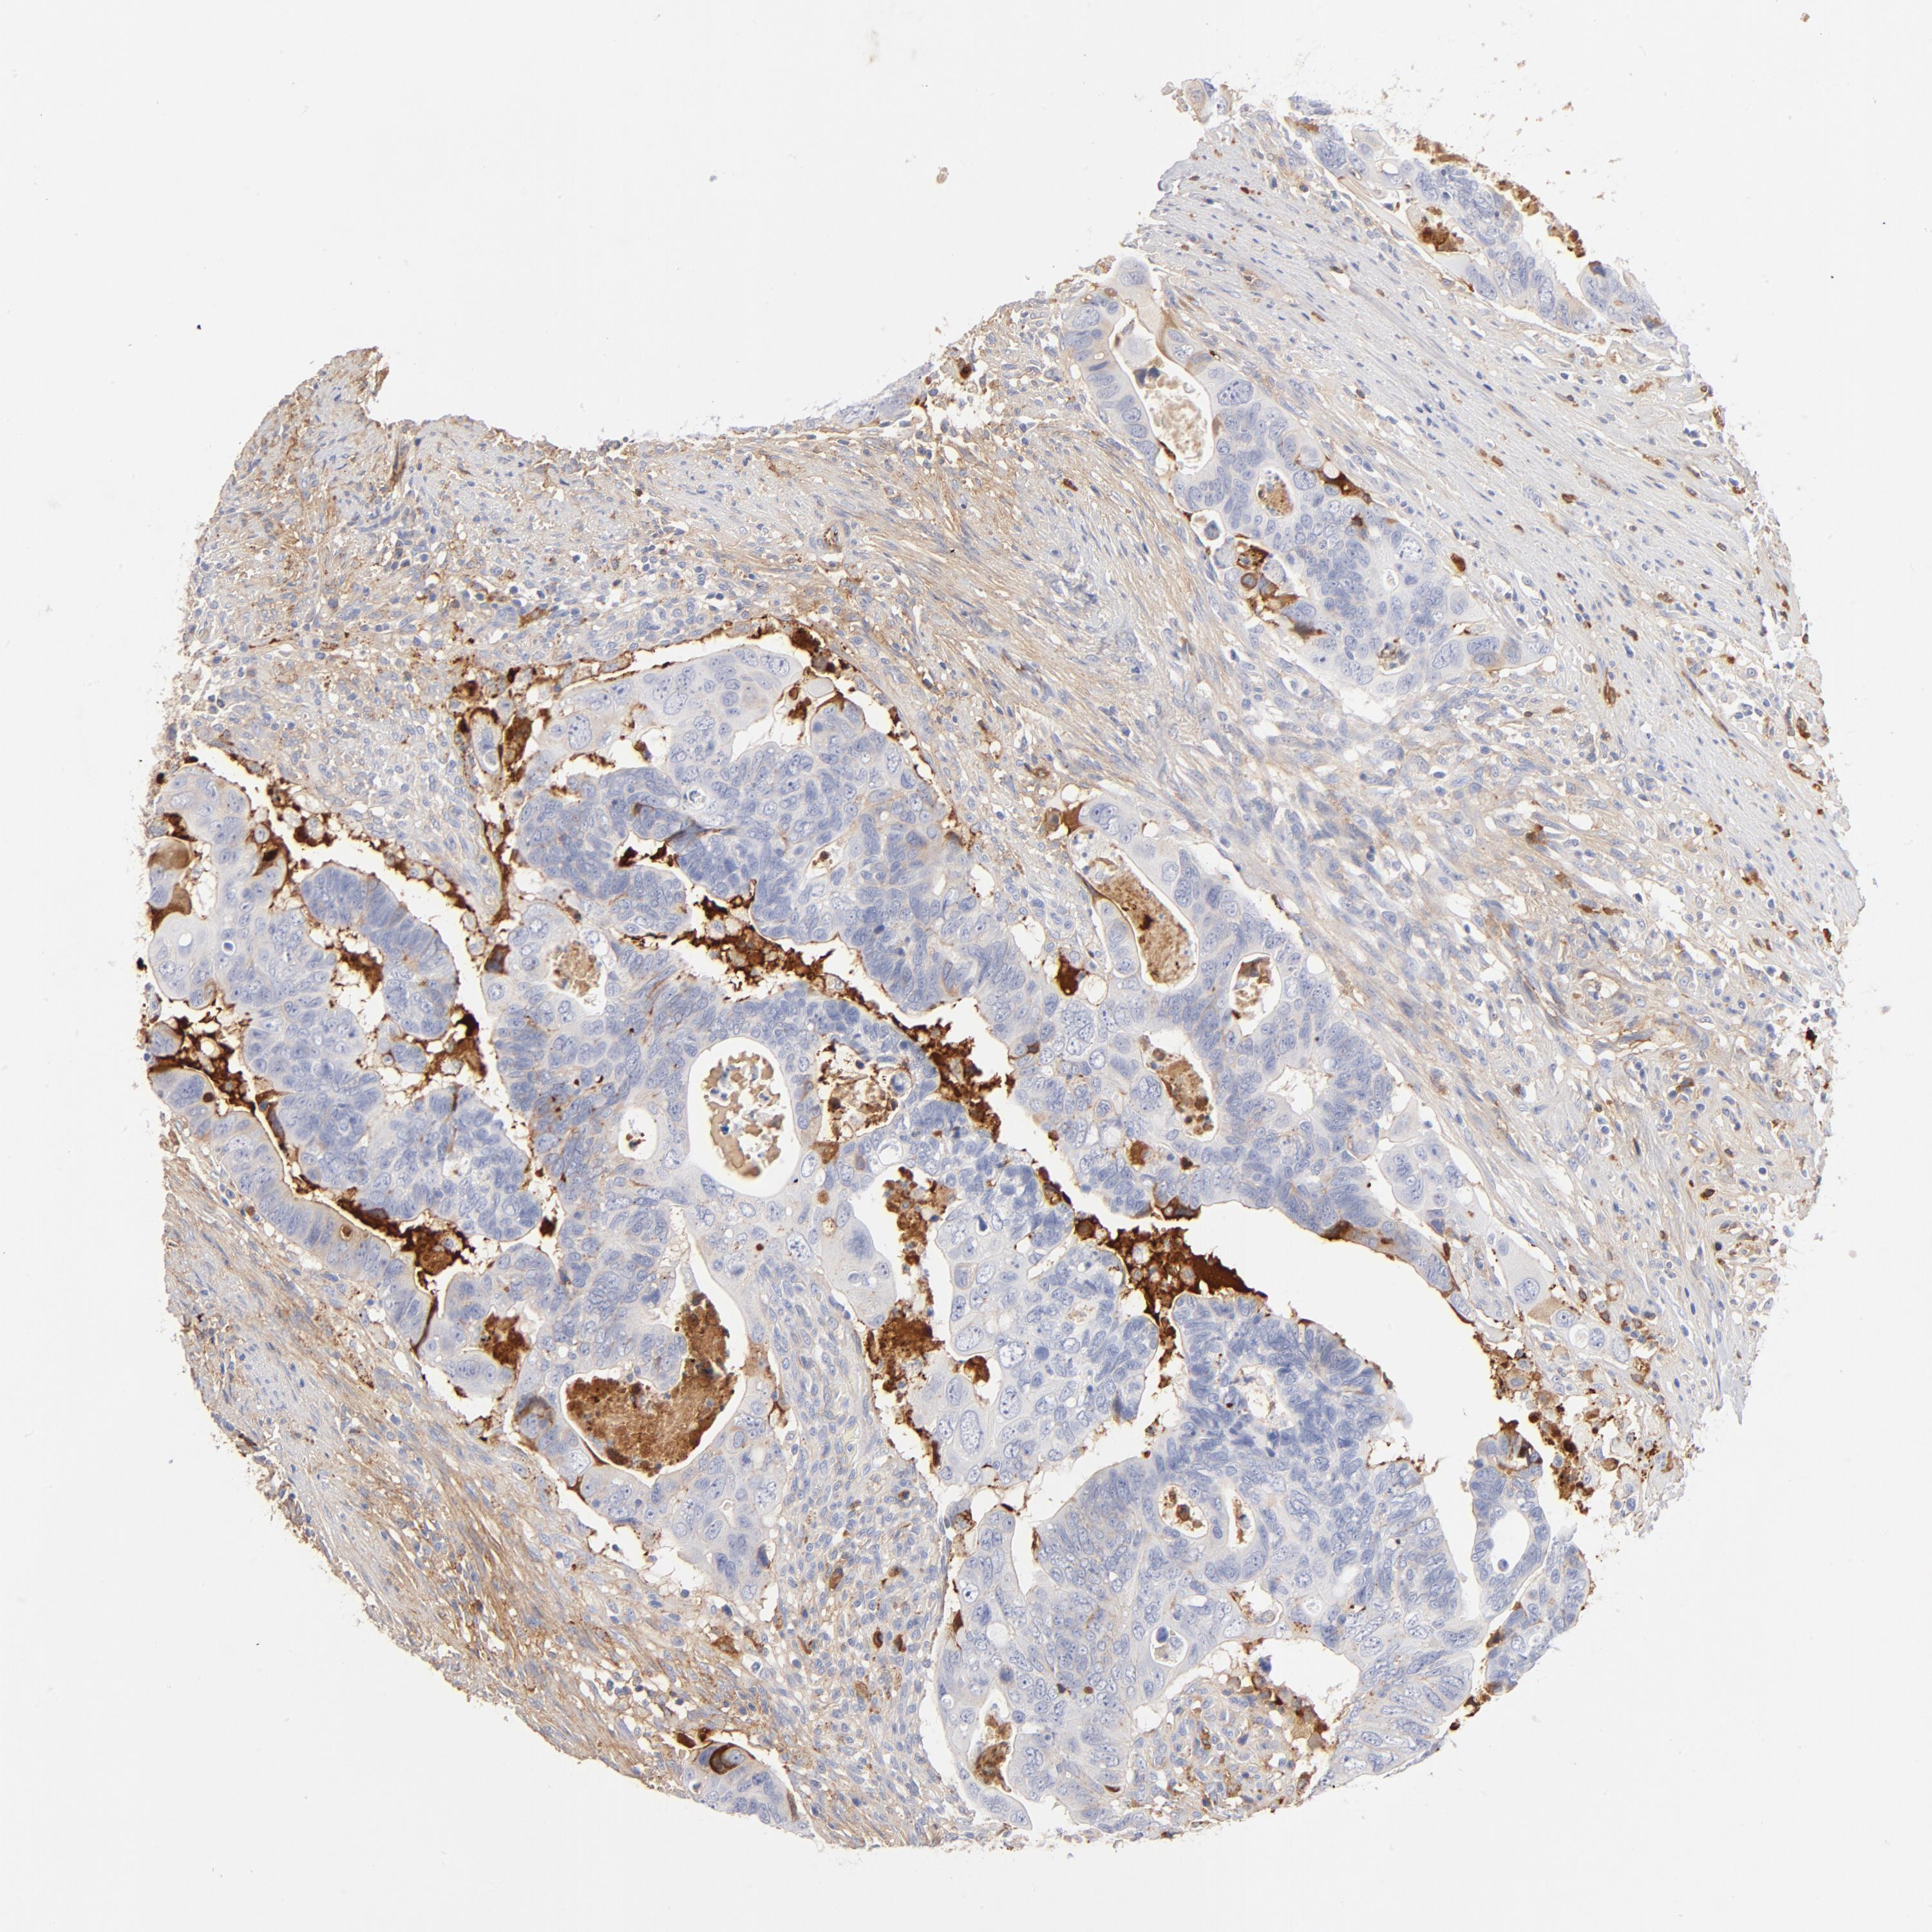

CANCER COLORECTAL CANCER Show tissue menu

Colorectal cancer

Human cancer

Colon adenocarcinoma